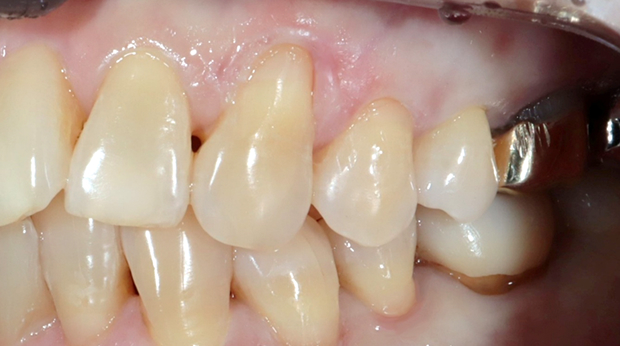

라미네이트

임플란트와 사랑니 발치는 외과적 시술로 잇몸을 절개하는 외과적 시술은

짧으면 짧을 수록 시술 후 붓기와 통증이 최소화됩니다.

치과의사 경력 14년차 구강외과 전문의가 빠르고 안전하게, 아프지 않게 수술해 드립니다.